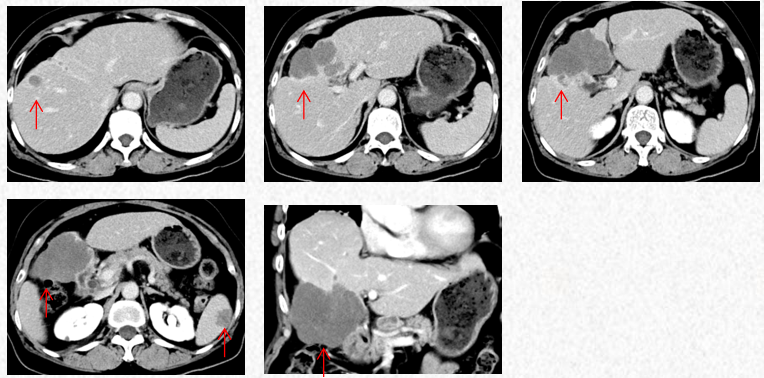

2022-12-01方案:斯鲁利单抗(200mg,Q3W)+安罗替尼(12mg QD,吃2周停1周)+卡培他滨(1g bid,D1-14)。右上腹痛较前逐渐减轻,第3疗程开始无需口服止痛药。

2023-3-19复查胸腹CT图片,最佳疗效评估为PR。

2023-5-22复查胸腹CT图片,疗效评估为SD,出现轻度双上肢麻木,可耐受。

2023-7-15复查胸腹CT图片,疗效评估为SD,轻度双上肢麻木,生活不受影响。

2023-3-19胸腹CT:肝肿物最大横截面积91*60mm,脾脏转移瘤(19*12mm)

2023-5-22胸腹CT:肝肿物最大横截面积86*58mm,脾脏转移瘤(19*12mm)

2023-7-15胸腹CT:肝肿物最大横截面积86*58mm,脾脏转移瘤(19*12mm)

在该例胆管癌治疗过程中,患者于2022年10月确诊为肝内胆管细胞癌IV期,肿瘤侵犯胆囊、结肠肝区及周围腹膜,且伴腹腔淋巴结、肝内、盆腔转移。患者拒绝使用一线GP或者GEMOX方案静脉化疗,一线采用斯鲁利单抗联合甲磺酸仑伐替尼治疗2个周期,疗效评估为PD,二线采用斯鲁利单抗联合安罗替尼和卡培他滨治疗,4程后疗效评估为PR,7程、9程后疗效评价为SD,二线方案治疗至今,PFS超过9个月且未达终点。该病例提示对于晚期胆管癌患者,斯鲁利单抗联合安罗替尼联合卡培他滨治疗可以为患者带来一定的生存获益。